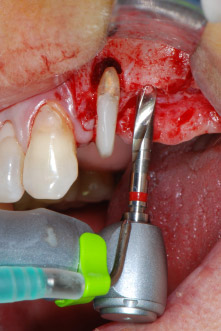

Si è mantenuta , tuttavia, l'idea iniziale di conservare entrambi i denti come appoggi temporanei del ponte durante il periodo di sei mesi per l'osteointegrazione degli impianti. In seguito la situazione si sarebbe assestata. In primo luogo, in un tentativo di risolvere il problema entro-periodontale, la superficie radicolare rimanente è stata attentamente sbrigliata con apparecchiatura piezoelettrica (Piezomed di W&H con l'attacco S1 a spatola, progettato in origine per l'erosione della parete laterale del seno mascellare) Fig. 4).

Quindi con lo stesso strumento si è passati ad abradere l'apice per rimuovere il tessuto apicale infetto residuo e per ridurre le possibili ramificazioni radicolari e canalari accessorie (apicetomia) (Fig. 5). Non è stato necessario riempimento retrogrado poiché si era appena ritrattato il riempimento ortogrado.

Fig. 4: Per conservare il dente come appoggio temporaneo, il periodonto è stato sbrigliato con apparecchiatura piezoelettrica...

Fig 5: ...e l'apice buccale del dente 24 è stato abraso con lo stesso strumento (apicectomia).